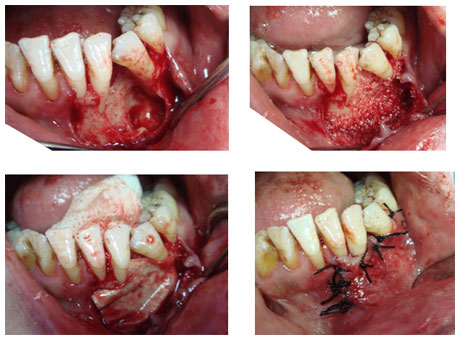

Gömülü işler

Sürme yaşı tamamlandığı halde

normal oklüzyonda yerini alamamış kemik

ve yumuşak doku içerisinde bütünüyle

veya kısmen kalmış olan dişlerdir.

Gömülü dişlerin ufak cerrahi

operasyonlar ile lokal anestezi altında

, steril şartlarda kliniğimizde çekimi

yapılmaktadır.